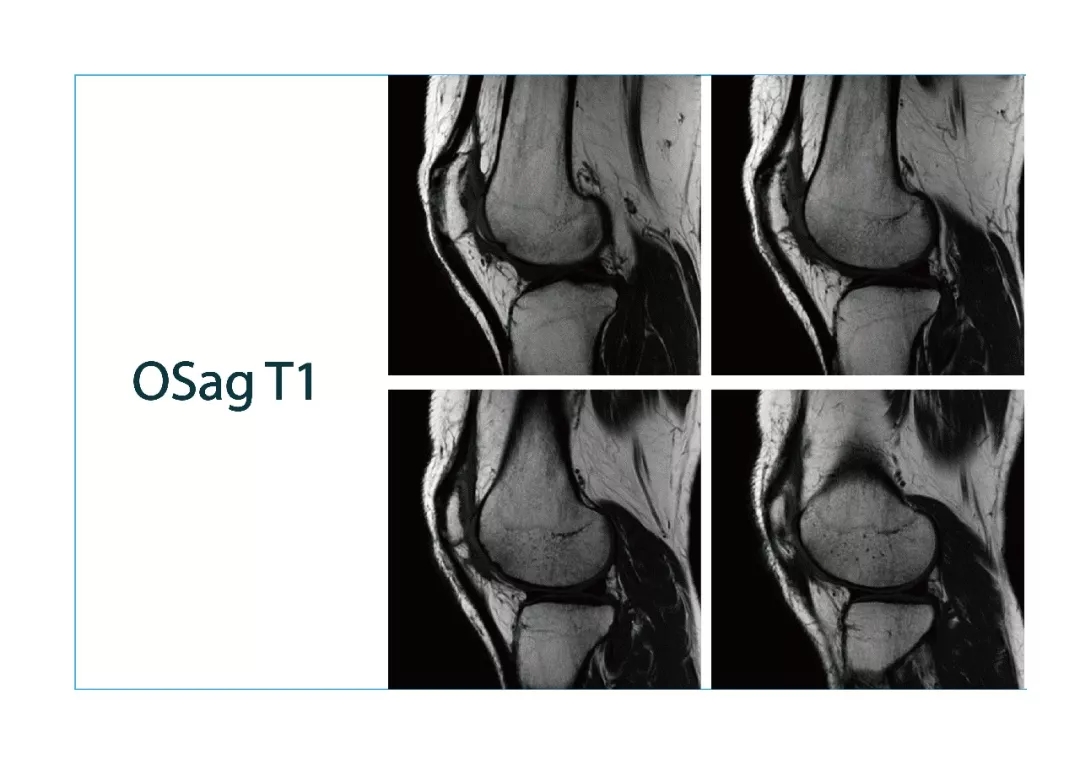

【朗润影像档案】磁共振影像病例分享(编号20180119)